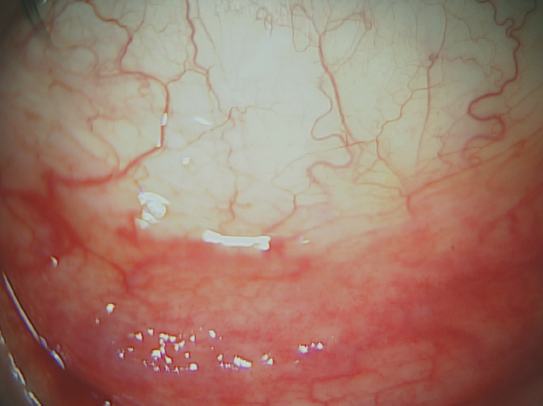

При биомикроскопии: правый глаз — конъюнктива век (рис. 5) и глазного яблока умеренно гиперемирована, мелкие фолликулы рядами на конъюнктиве нижнего века и переходной складке, имеются отдельные белёсые участки атрофии конъюнктивы века, отделяемого нет; левый глаз — конъюнктива не изменена, фолликулов нет, отделяемого нет. В обоих глазах не выявлено патологии со стороны роговицы и глубжележащих отделов. Флюоресцеин не прокрашивал конъюнктиву и роговицу в обоих глазах, но при использовании бенгальского розового выявлялись зоны повреждения эпителия бульбарной конъюнктивы правого глаза с носовой стороны и конъюнктивы переходной складки этого же глаза. LIPCOF-тест: степень 2 — на OD, степень 1 — на OS.

Рис. 5. Состояние конъюнктивы нижнего века при первичном осмотре

Fig. 5. Lower eyelid conjunctiva condition at the time of initial examination